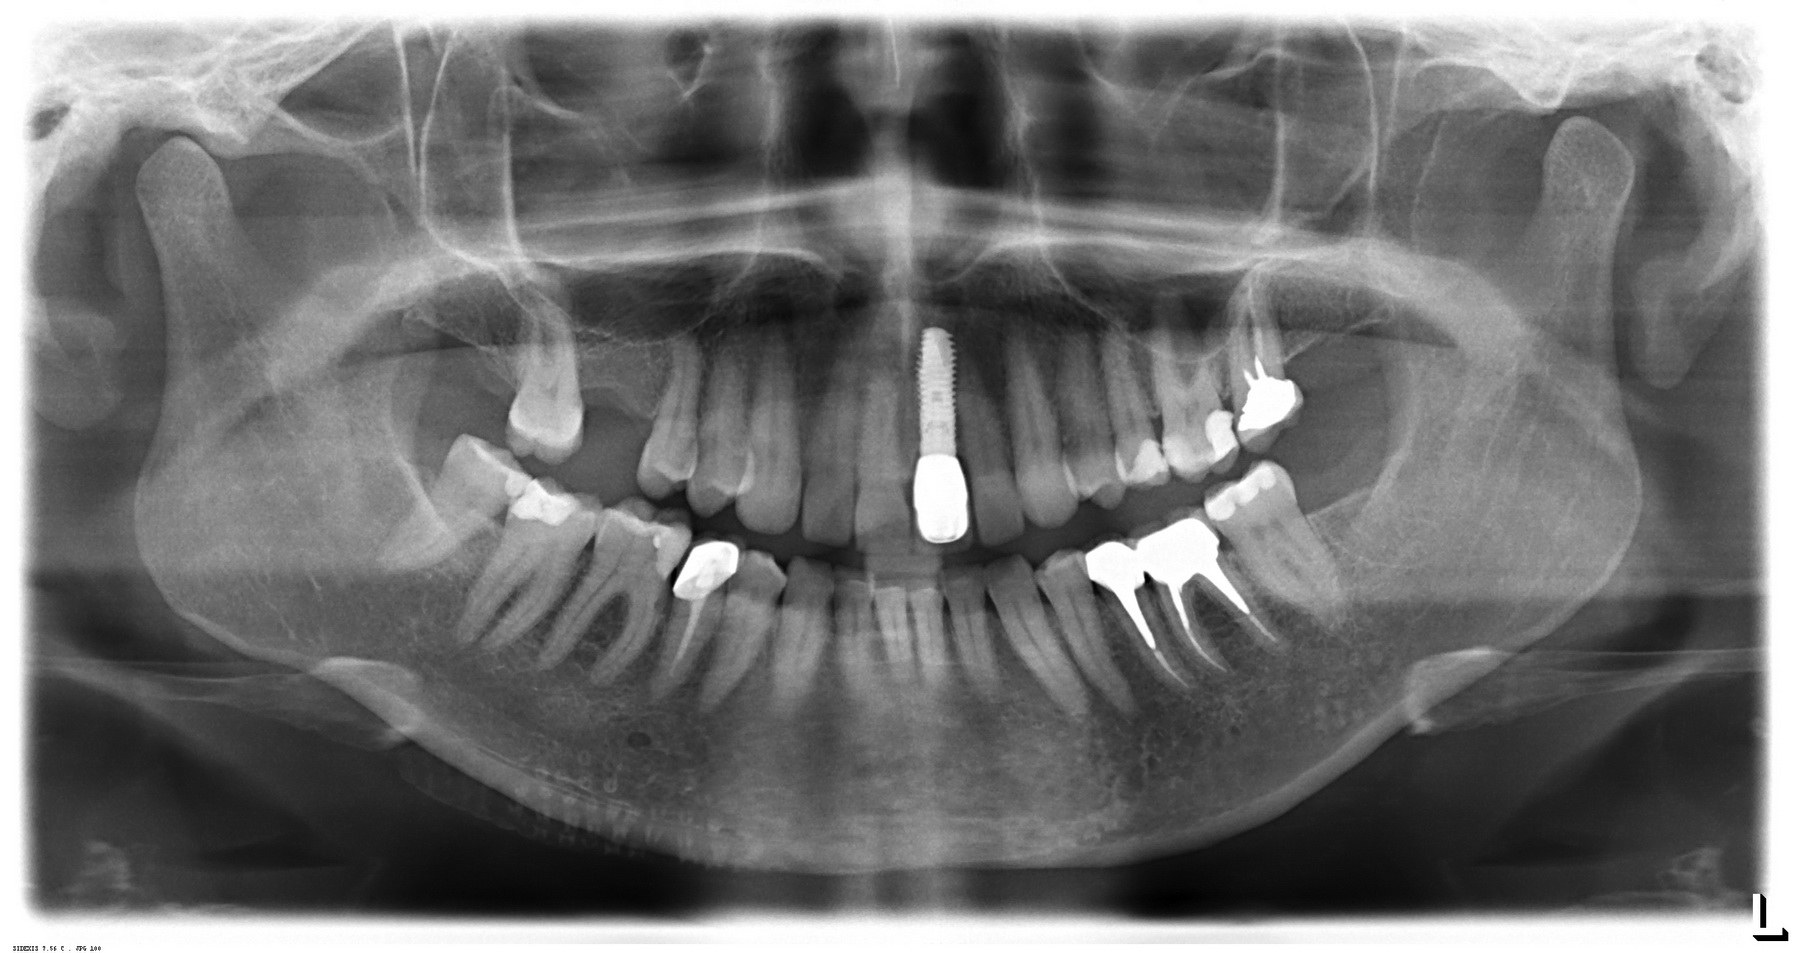

Важным диагностическим исследованием является ортопантомограмма или «панорамный снимок»:

Назначение ортопантомографии точно такое же, как и у прицельных снимков. Но более масштабное, ибо позволяет увидеть всю зубочелюстную систему целиком. Современные снимки делаются на цифровом оборудовании, и это также позволяет существенно снизить лучевую нагрузку на пациента. Для сравнения: чтобы получить хотя бы половину допустимой годовой лучевой нагрузки, нужно делать ортопантомограмму каждый день в течение месяца. То есть, около тридцати снимков за полгода. Понятное дело, никто такого количества снимков не делает.

ВАЖНОЕ ЗАМЕЧАНИЕ! Несмотря на всю прелесть и, казалось бы, наглядность ортопантомографии, ее НЕЛЬЗЯ использовать для планирования имплантации или сложного хирургического лечения (остеопластики, синуслифтинга и т. д.). Дело в том, что данный снимок сильно искажает расстояния и отношения между различными анатомическими структурами, а также не дает представления о целом ряде важных для хирургии параметров. Подробнее об ортопантомографии можно почитать тут.